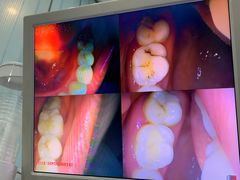

• 土豆口腔(凤凰北总店)

• -土豆口腔(凤凰北总店)

匿名用户 | 22-11-06